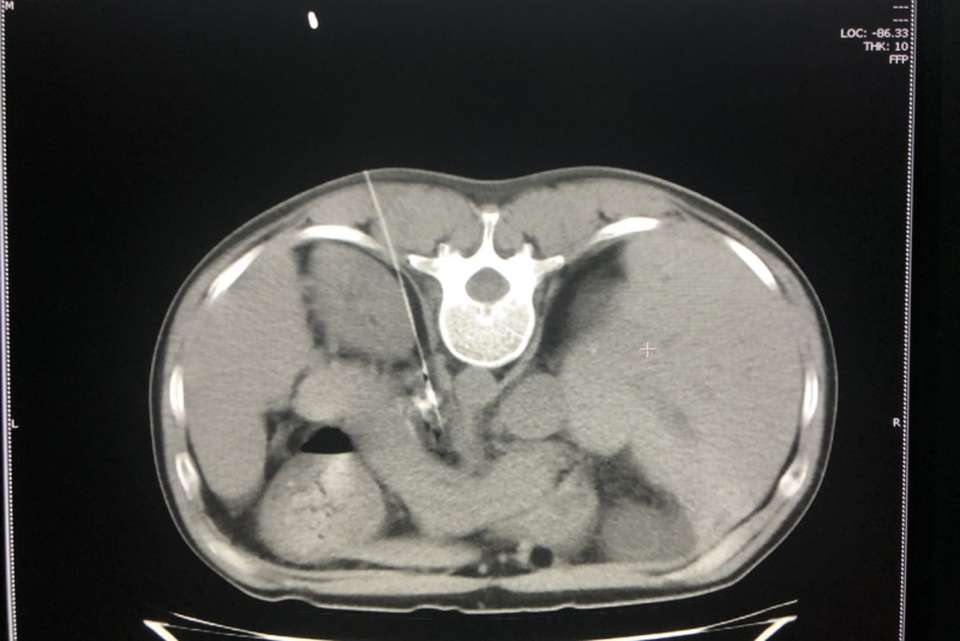

Quá trình thực hiện can thiệp diệt đám rối thần kinh thân tạng trên phim chụp cắt lớp

“Đám rối thân tạng (hay đám rối dương – Celiac Plexus) là một đám rối thần kinh lớn và quan trọng trong ổ bụng. Đám rối tạng vây quanh động mạch thân tạng và động mạch mạc treo tràng trên, đóng vai trò là trung tâm chuyến tiếp cảm giác đau của các tạng nằm tầng trên đại tràng ngang như tụy, dạ dày thực quản, gan, tuyến thượng thận… Do đó, can thiệp diệt đám rối thần kinh thân tạng đối với những bệnh nhân có bệnh lý ung thư vùng bụng trên (tầng trên mạc treo đại tràng ngang) như ung thư gan, tụy, thực quản, dạ dày, túi mật, thận, ung thư di căn đến tạng, hạch di căn chèn ép vào đám rối thân tạng… bị đau dai dẳng vùng bụng, lưng cục bộ bằng cồn tuyệt đối dưới hướng dẫn của cắt lớp vi tính có tác dụng giảm đau nhanh chóng và lâu dài hơn so với phương pháp điều trị bằng thuốc nội khoa thông thường”. – Bác sĩ CKI Lê Tiến Hưng – Phó Trưởng Khoa Chẩn đoán hình ảnh Bệnh viện Bãi Cháy cho biết.

Kỹ thuật này có độ khó cao, yêu cầu đường kim chọc vào đám rối thân tạng phải chính xác tuyệt đối, tránh làm tổn thương gan, tạng, chọc thủng tạng hoặc mạch máu trong quá trình can thiệp.

Đội ngũ bác sĩ điện quang can thiệp phải có trình độ cao, giàu kinh nghiệm, nắm vững cấu trúc giải phẫu và hệ thống máy chụp cắt lớp vi tính hiện đại để có thể quan sát, kiểm soát đường chọc kim can thiệp, bơm cồn tuyệt đối 100% đốt cháy đám rối thần kinh thân tạng một cách chuẩn xác.